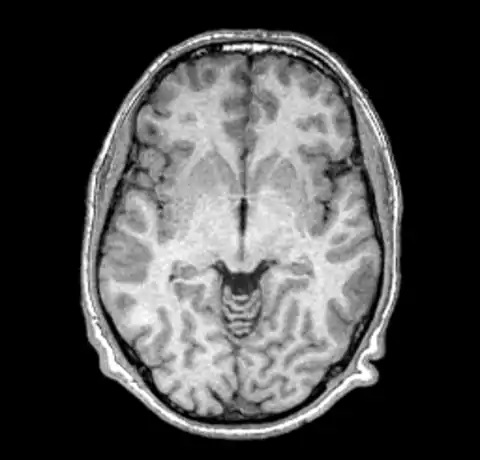

B0 non-uniformity is difficult to detect when simply looking at images without the assistance of a judiciously ranged color map. In our test case we'll start with a simple T1 MPRAGE image from a 1.5T Siemens scanner.

The above image and all the images here were created using mincpik in a similar fashion to the below.

mincpik -scale 2 original.mnc -slice 150 -image_range 10 80 original.png

Note that it is difficult to pick the non-uniformity in the image unless you look carefully at the intensity of the white matter in the lower parts of the image. In order to correct this image we run nu_correct with the default parameters.